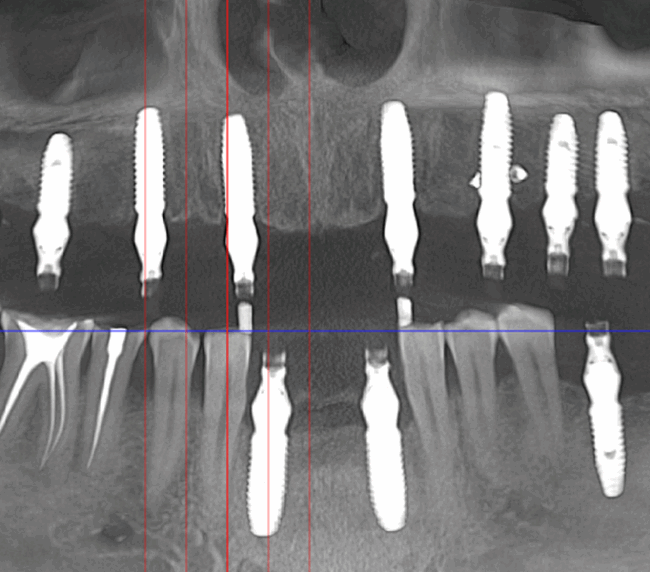

Tomografie (CBCT)

Caz 2